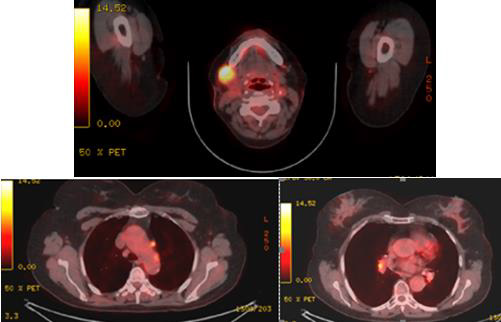

We present a woman at the age of 63 with a painless swelling in the right submandibular area with a discharge since three months. Of the examination, indirect laryngoscopy, mesopharygoscopy and nasopharyngoscopy does not establish a pathological finding. In the palpation of the neck in the right submandibular region there is an increased lymph node with a diameter of more than 3 cm. The CT with contrast diagnosed two suspected for metastatic lymph nodes in the right cervical area (Figure 1). After surgical excision of cervical lymph nodes, the biopsy proves metastasis from small cell anaplastic /neuroendocrine carcinoma. Immunohistochemical study reports: tumor cells express synaptophysine and CD56, focally positive to EМА and pancitokeratin, but negative to TTF1, S100 protein, CК 20 and CD45 (Figure 2 & Figure 3). The patient is judged to conduct 3 courses of chemotherapy (Ch), and then restaging. In April 2021, from a PET/CT data for a metabolic active lesion located right retromandibular, most likely a metastatic lymph node. Metabolic active hyleric and mediastinal lymph nodes are reported. [Figure 4].

Figure 4: PET/CT (April 2021) data for a metabolic active lesion located in the right retromandibular area, most likely a metastatic lymph node. Metabolic active hyleric and mediastinal lymph nodes.

Prognosis - Merkel cell carcinoma (MCC) is a rare but highly aggressive neuroendocrine carcinoma of the skin, with frequent recurrences, metastases, and a high mortality rate [46]. The prognosis is rather poor. Stage of disease at presentation predicts overall survival [47]. The typical clinical development of the MCC is progression of the primary tumor accompanied by early and frequent metastases in regional lymph nodes [5,6,21]. Local recurrences are very common, occurring in up to 44% of patients. The 5-year survival rate is between 30% and 64%. Mortality rate of MCC exceeds that of any other skin cancers [48]. In our clinical case, after two months despite the surgical selective dissection, PET/CT proves not only the metabolic active submanibular lymph node which recurs, but also hyleric and mediastinal lymph nodes (Figure 4).